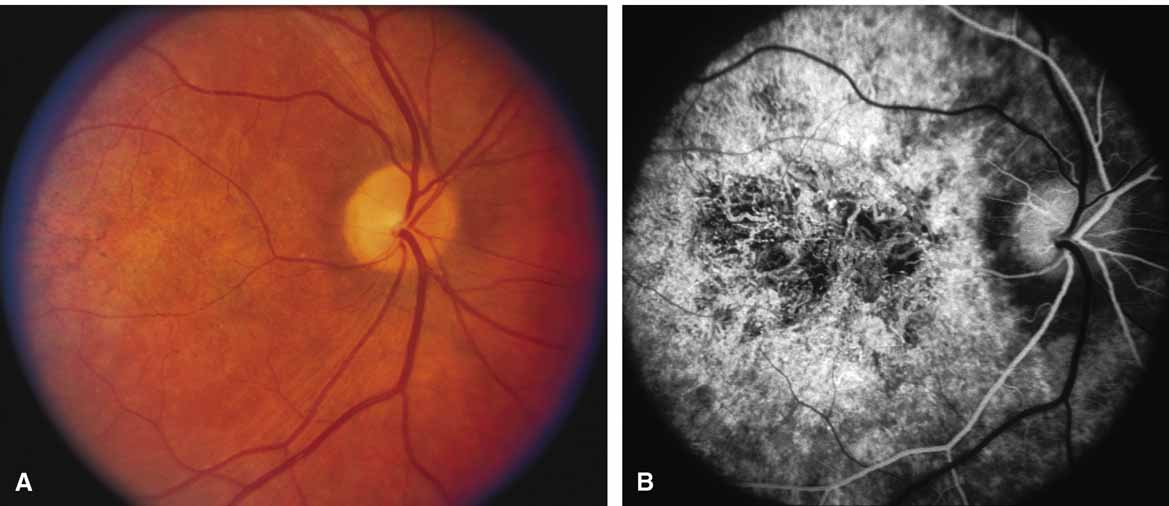

Choroideremia (gene symbol CHM; MIM No. 303100) is an X-linked disorder that is characterized by the onset of night blindness in the first or second decade of life followed by slowly progressive atrophy of the choroid and retina that usually results in legal blindness by midlife and near virtual blindness in later years. The disorder begins with a diffuse atrophic process involving retinal pigment epithelium and choriocapillaris (Figs. 12A, 12B, 12C, and 12D) but eventually results in near total vascular choroidal atrophy (Fig. 13A). The fundus does not show the sharp border or transition area that is characteristically seen with gyrate atrophy. The peripheral visual field is depressed and eventually becomes severely constricted. The ERG and EOG are abnormal early in the course of the disease.